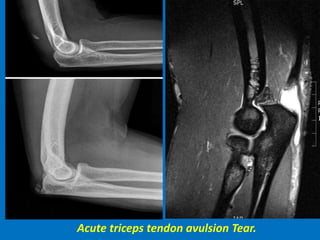

Triceps avulsion fracture.

Acute triceps tendon avulsion Tear.

Complete triceps tendon tear.

Triceps tendon tear with hemorrhage.